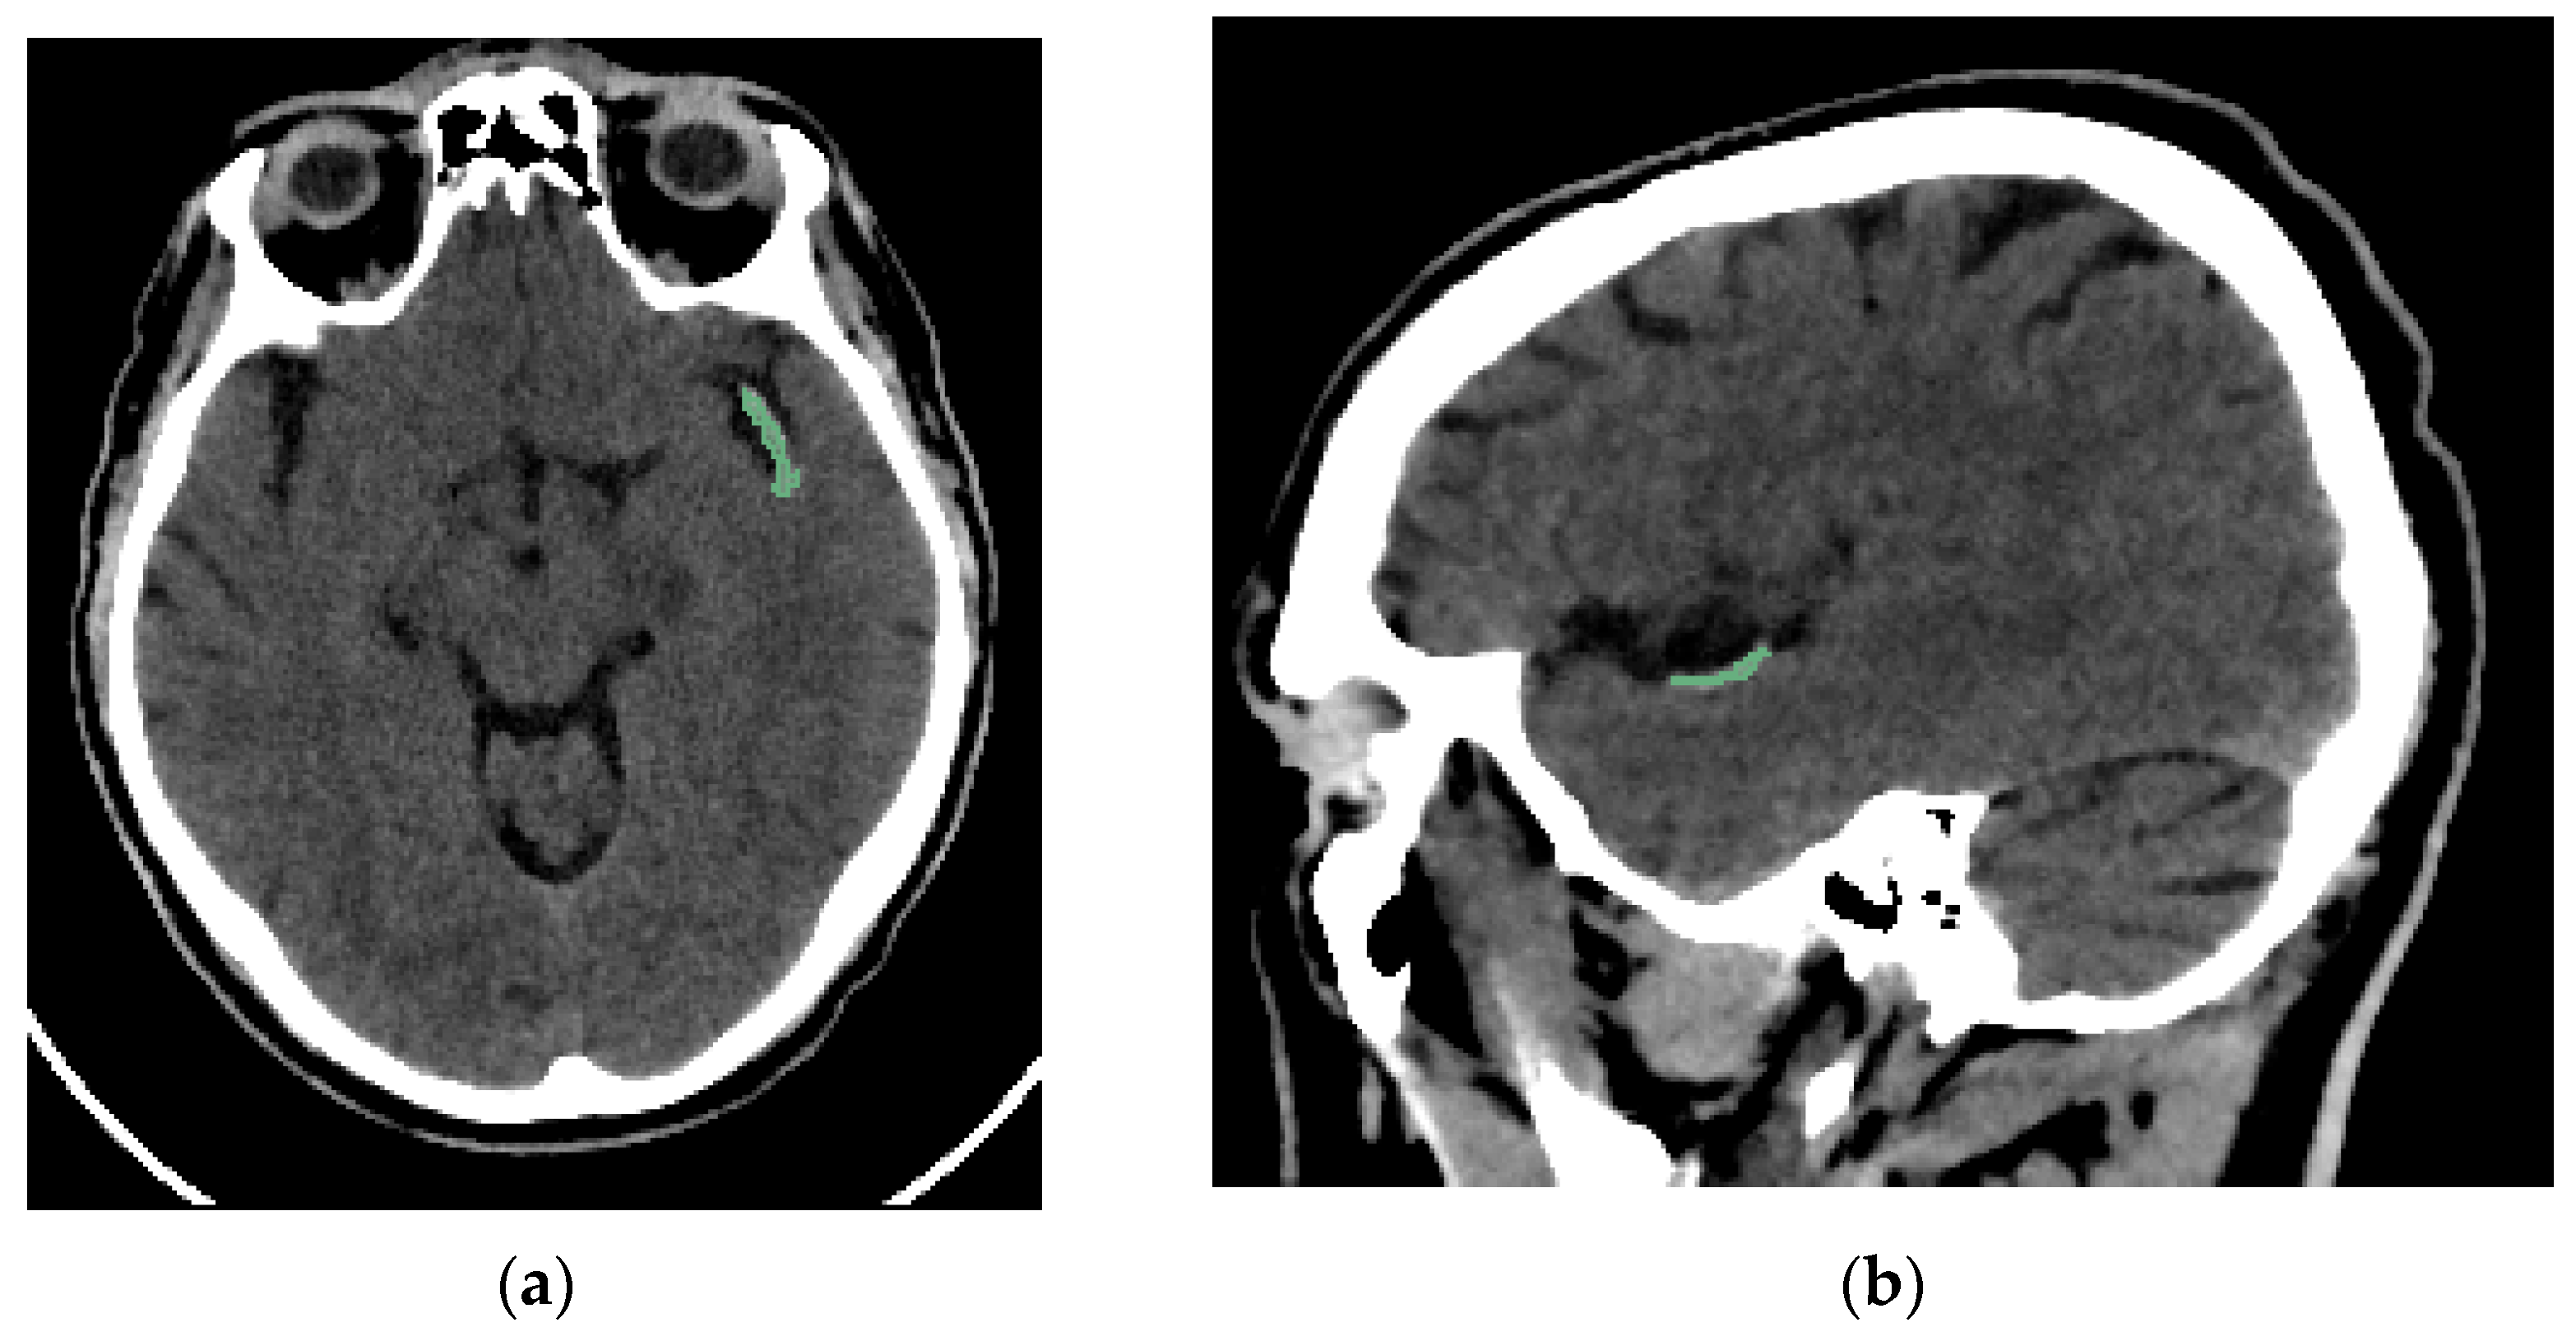

Two interventional neuroradiologists and a radiology resident who had undergone specialized training performed semi-automated segmentation of each thrombus. The segmentation was conducted using the open-access software 3D Slicer (version 5.2.2, Massachusetts, USA) [16]. The software includes a segmentation tool (Level Tracing tool) that enables semi-automatic segmentation based on automatic edge detection. The region of interest segmented was the clot visible on NCCT in patients with AIS (Figure 2). Segmentation was performed in the axial, sagittal, and coronal planes (Figure 3). The window width and center were set to 100 and 50 HU, respectively.

Figure 2. Brain NCCT of the same patient as in Figure 1, with the thrombus segmented. The segmentation was performed using the “Level Tracing” tool of 3D Slicer. (a) Axial NCCT with thrombus segmented. (b) Sagittal NCCT of the same patient with the thrombus segmented.